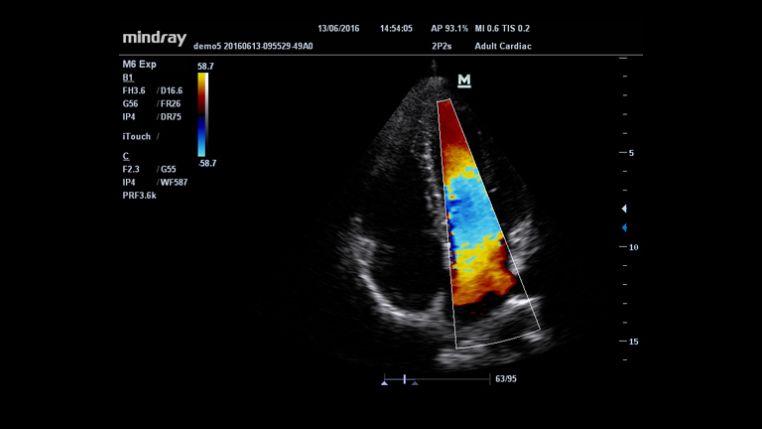

iTouch™ (automatyczna optymalizacja obrazu)

Funkcja ta pozwala uzyskać natychmiastową automatyczną optymalizację obrazu w trybach B, Kolorowego Dopplera i PW (Spektralnego Dopplera Fali Pulsacyjnej) poprzez naciśnięcie jednego klawisza.